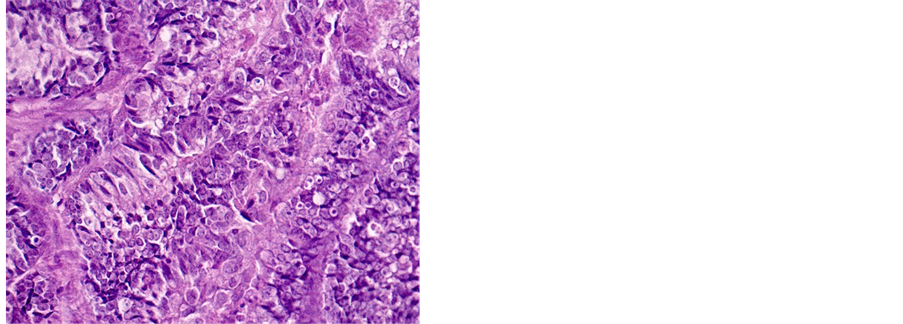

Table 2 shows the distribution of histological types of cancers diagnosed during the study. A total of 1687 (81.18%) cases of squamous cell carcinoma (SCC) and 269 (12.95%) cases of adenocarcinoma (ADK) have been identified (Figures 3-5).

Figure 5. Well differentiated ADK (a) 200×, (b) 400×.